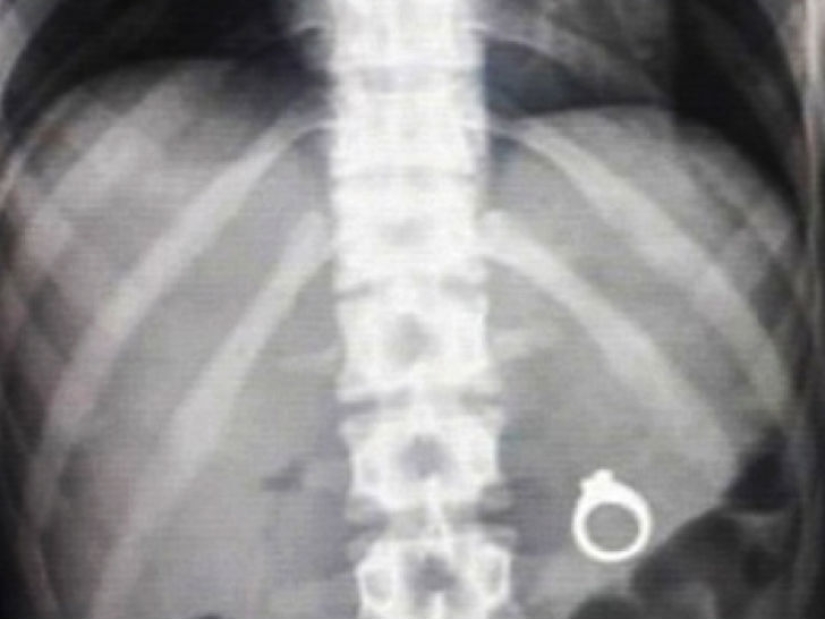

Many men want to be romantic and make an offer to their half in some unusual way. And many people use, for example, food to hide a surprise in the form of a ring there. So, men, make an offer before your betrothed decides to try this dish with a surprise.